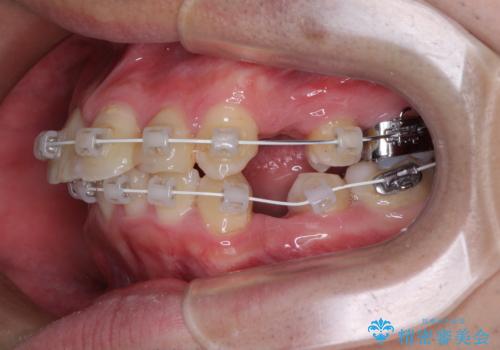

- 審美装置

口元はやや突出感があったため、上下左右の第一小臼歯4本を抜歯してワイヤー矯正にて抜歯矯正を行うこととしました。

また、左右ともに最後臼歯が交叉咬合になっており、外側に飛び出している上顎の最後臼歯を補助装置を利用して、積極的に内側に引き込むようにしました。